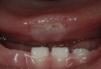

Exploración físicaPresentaba una úlcera redondeada, de bordes bien definidos, indurada, de 1×1cm de diámetro en la cara ventral de la lengua, coincidiendo con los dientes incisivos inferiores (fig. 1). En la base de dicha lesión se observaba un exudado blanquecino y 2 úlceras lineales más profundas. No se palpaban adenopatías cervicales ni presentaba otras lesiones en la piel ni en las mucosas. El niño presentaba un buen desarrollo pondo-estatural y la exploración neurológica fue normal.

Evolución y tratamientoEl paciente recibió tratamiento odontológico con pulido de los bordes de los dientes incisivos. A las 4 semanas la lesión había disminuido de tamaño (fig. 2) desapareciendo por completo al mes siguiente.